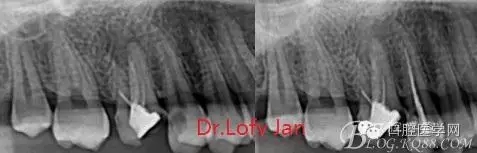

《數(shù)字化根尖片、曲面斷層片、CBCT測量牙齒長度準(zhǔn)確性的比較研究》文中顯示:平行投照數(shù)字化根尖片影像長度和牙齒實(shí)際長度之間無顯著性差異(P0.05);數(shù)字化曲面斷層片影像長度和牙齒實(shí)際長度之間有顯著性差異(P0.05),平均失真率為17.05%。CBCT冠狀面測量結(jié)果中除上頜前磨牙區(qū)、下頜前磨牙區(qū)與真實(shí)長度差異無統(tǒng)計(jì)學(xué)意義(P0.05)外,其余6個(gè)分區(qū)差異均有統(tǒng)計(jì)學(xué)意義(P0.05);矢狀面測量結(jié)果中上頜磨牙區(qū)、下頜磨牙區(qū)、下頜前磨牙區(qū)、下頜尖牙區(qū)、下頜前牙區(qū)與真實(shí)長度比較差異均有統(tǒng)計(jì)學(xué)意義(P0.05)。結(jié)論平行投照數(shù)字化根尖片較曲面斷層片和CBCT能更加精確地反映牙齒的真實(shí)長度。

病例分析:曲面斷層片在x線輔助診斷與檢查中目前大多數(shù)文獻(xiàn)和著作都建議只能作為初診拍片檢查手段,不能作為終末疾病的確診與手術(shù)療效的評價(jià)指標(biāo),臨床大部分中小型門診都因?yàn)樵O(shè)備不齊全導(dǎo)致信息偏差很大。